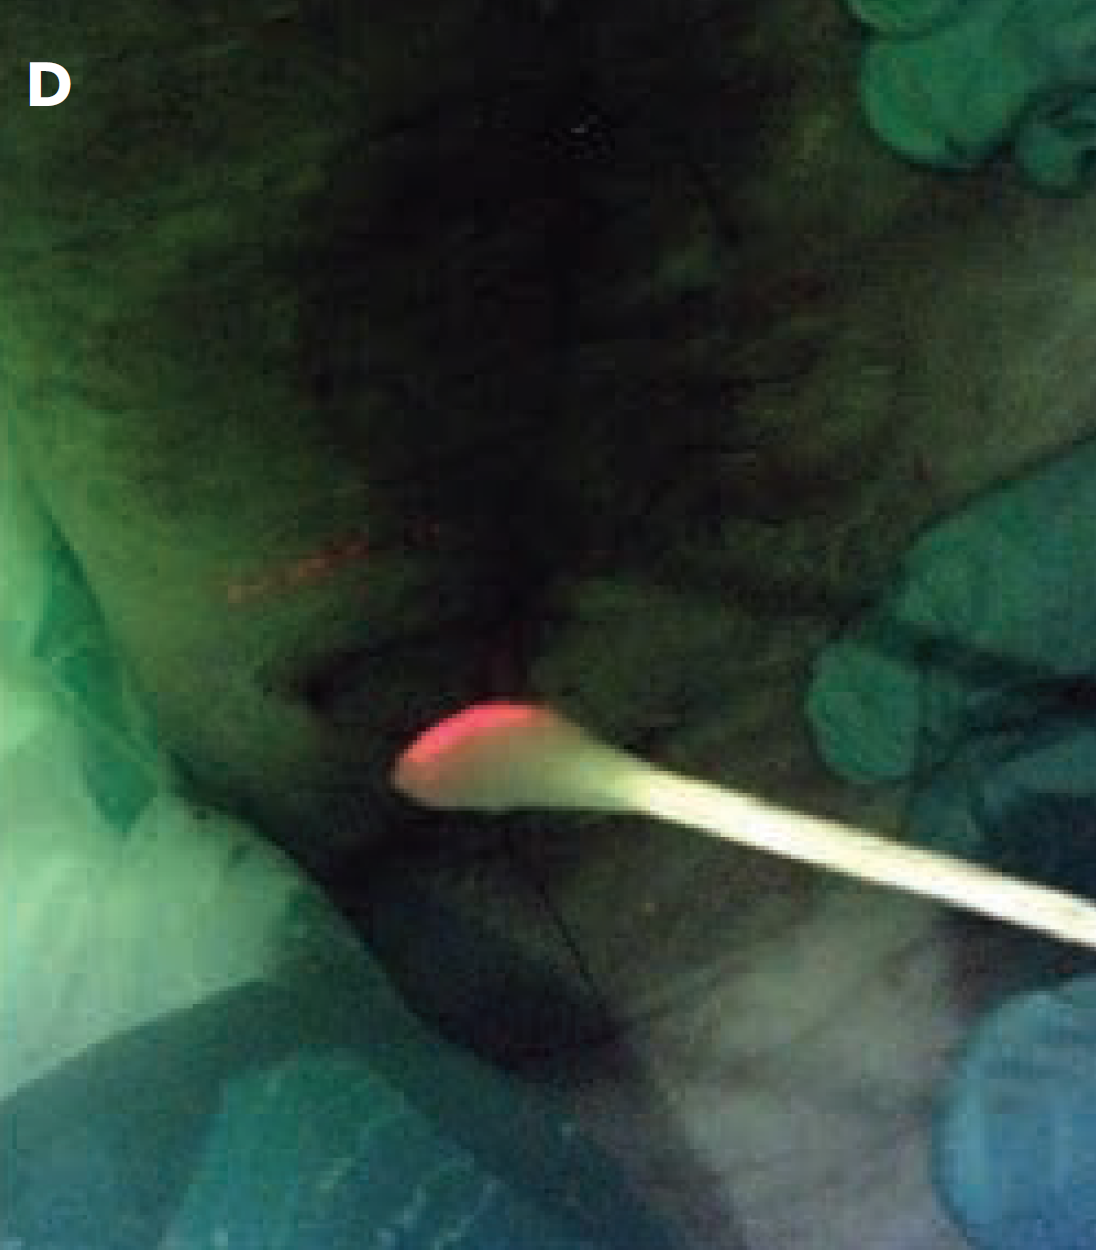

The “C-Swab” test: a technique for identifying bacteria in sinus tracts or tunneled wounds utilizing a cotton swab and bacterial fluorescence imaging

Andersen C. and McLeod K. Wounds 2025